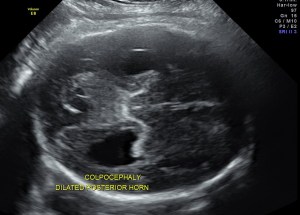

prominent ventriculomegaly of posterior horns of both lateral ventricles – colpocephaly

- disproportionate enlargement of the occipital horn,

The increased separation of the normal-sized bodies and the enlargement of the atria and occipital horns of the lateral ventricle result in a typical ultrasound image. Upward displacement of the third ventricle is a very specific sign36 but presents only in 40% of fetuses.